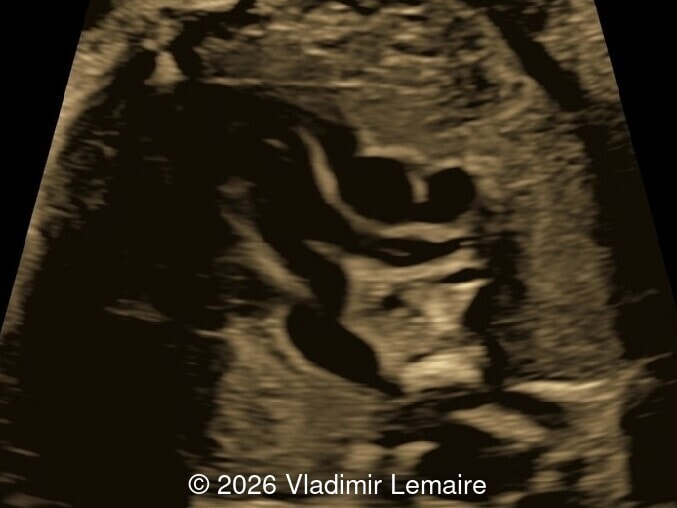

Surface mode rendering looking into the brain of the same fetus with the vein of Galen aneurysmal malformation.

Image 1 Surface mode rendering looking into the brain of the same fetus with the vein of Galen aneurysmal malformation.

Our imaging revealed enlargement of the fetal heart with dilation of the superior vena cava. On further evaluation, we identified an elongated anechoic cystic structure in the midline of the head, without mass effect on the surrounding structures. Color doppler demonstrated an arteriovenous fistula between the deep choroidal arteries and the embryonic median prosencephalic vein of Markowski. The vein of Galen aneurysmal malformation was likely the contributing factor to the cardiac enlargement. Cardiac function was, however, preserved and hydrops not present. Additional images are shown below.

We present a case of Vein of Galen Aneurysmal Malformation (VGAM).